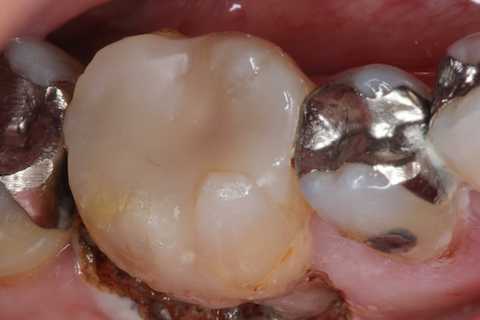

残根上のCR8 2025.10.28